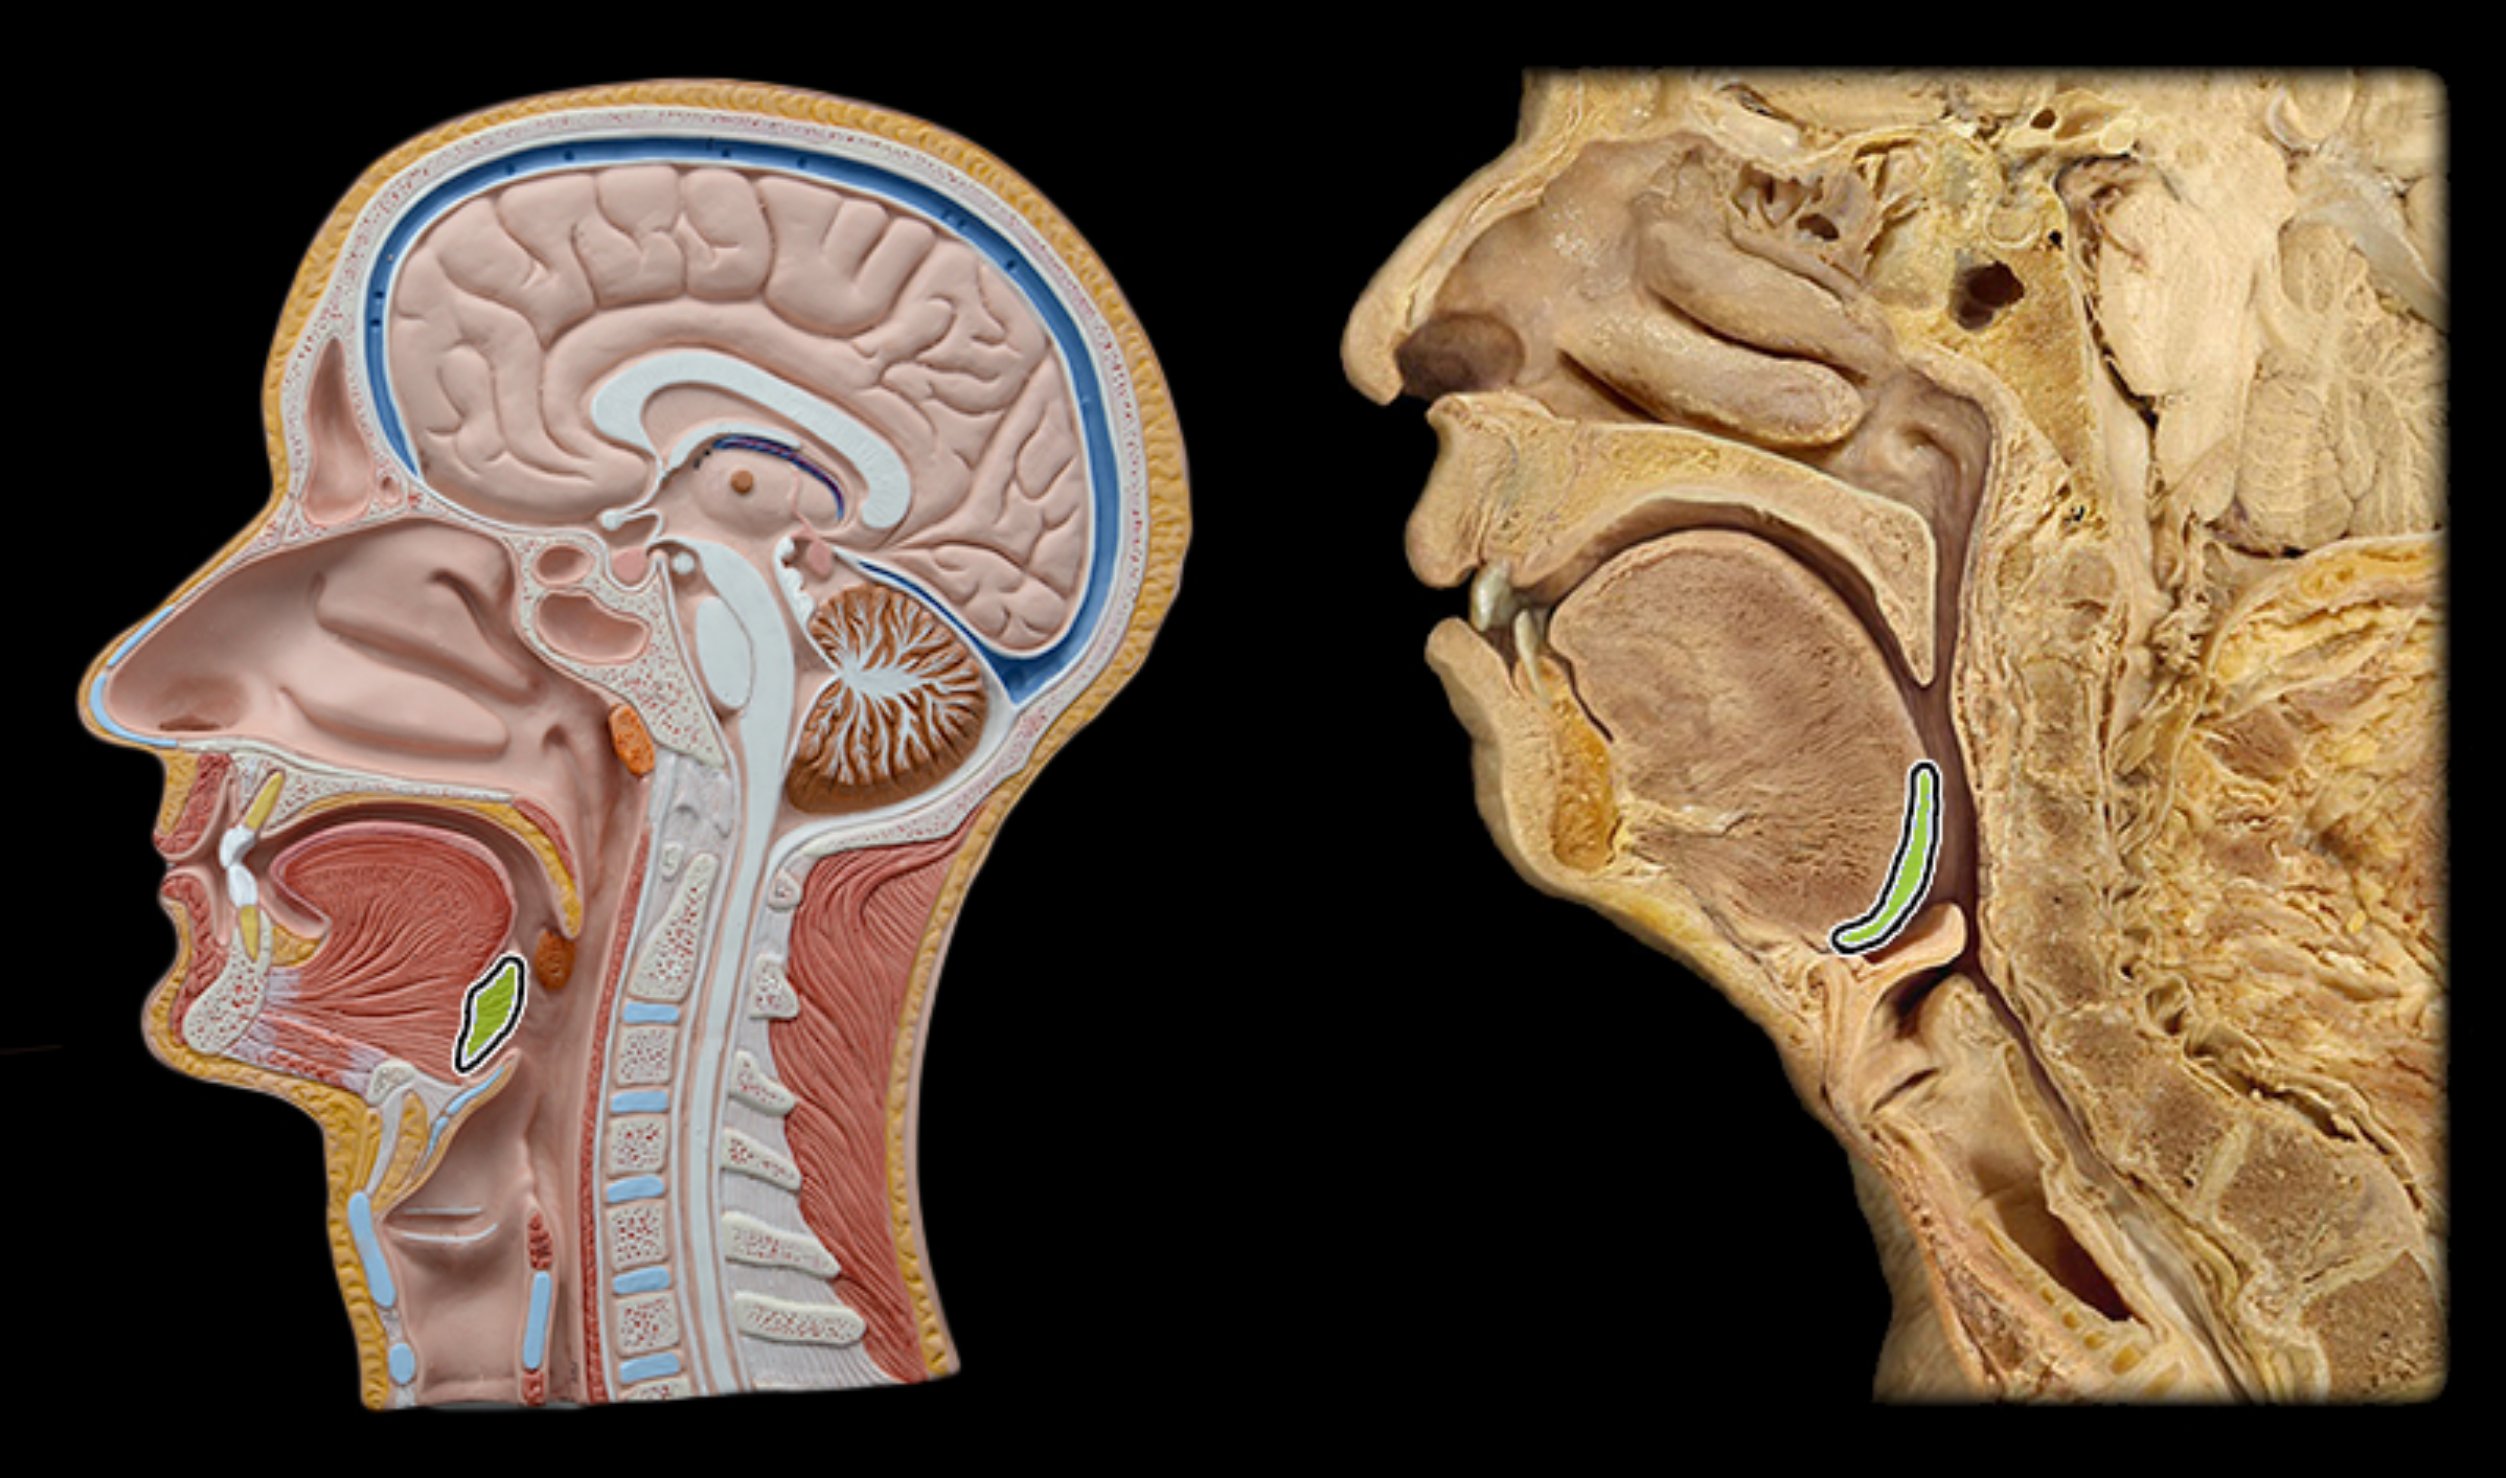

Lingual tonsil

Palatine tonsil